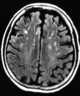

Chronic punctate sialadenitis

Parotitis is an inflammation of one or both parotid glands, the major salivary glands located on either side of the face, in humans. The parotid gland is the salivary gland most commonly affected by inflammation. [Source: Wikipedia ]